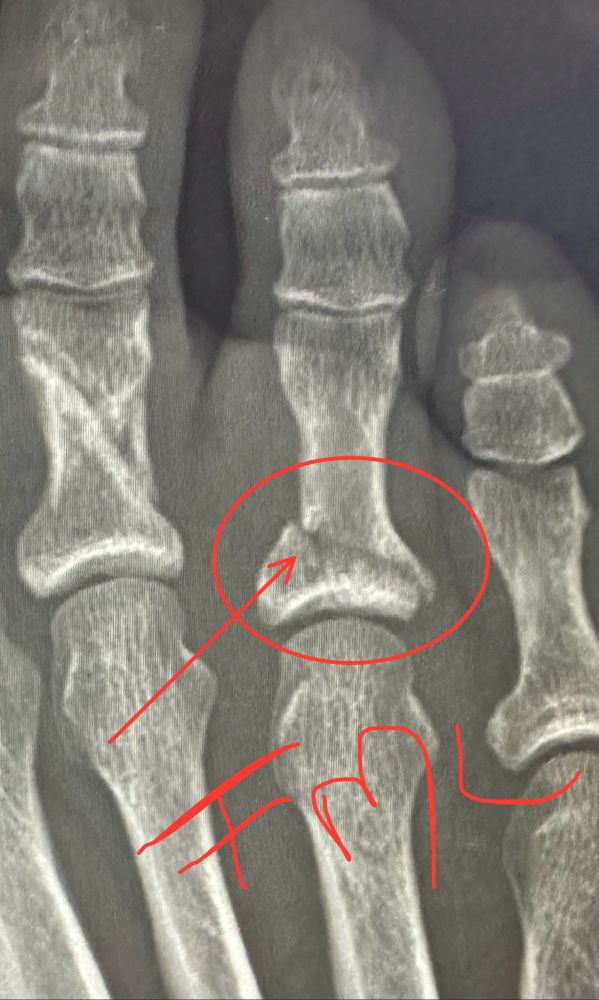

Leave it to me to break a SECOND toe in three months by accidentally kicking a weight (barefoot) whilst teaching a yoga sculpt class. Yeah… I’m f’ing good like that. 🤦🏼‍♀️😖🤦🏼‍♀️😖🤦🏼‍♀️ Namaste, indeed.